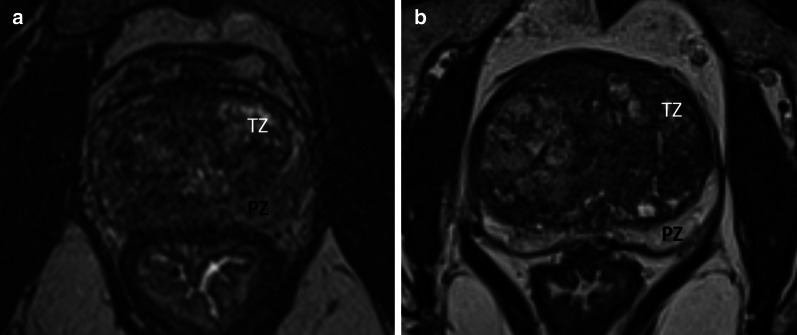

Fig. 5.

Influence of intensity signal ratio between the TZ and the PZ on zonal differentiation, a Moderate signal difference between zones (signal ratio = 0.98); b Marked difference in signal intensity, facilitating zonal differenciation (signal ratio = 0.37)

A low squared TZ to PZ contrast was significantly associated with a higher segmentation variability (ρ = 0.5 (CI 95% = [0.23; 0.7], p-value = 0.01 and 0.45 (CI 95% = [0.17; 0.67], p-value = 0.03) for the pairwise method and the consensus comparison (STAPLE method).

No significant difference was found when considering the impact of the presence of tumor (p-value = 0.53 for the mean DSC on the WG). Finally, a retro-urethral lobe protruding into the bladder showed no significant influence on segmentation variability (p-value = 0.08 for the mean DSC on the WG). These results are detailed in Table 3 and illustrated in Figs. 4, 5 and Additional file 4 and Additional file 5.